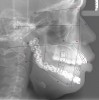

At that appointment, a cone-beam computed tomography (CBCT) scan and other radiographs were obtained. The radiographic findings revealed a multilocular expansile radiolucency that extended further than what was observed in the initial clinical examination. The radiolucency appeared to displace the inferior alveolar canal and lower border and had expanded but not perforated the mandibular cortex (Figure 3). The diagnostic work-up initially consisted of lesion aspiration. Then, multiple pieces were collected by incisional biopsy. The pathology report showed the histologic presence of epithelial islands that mimicked the enamel organ within a fibrous collagenized stroma. There were peripheral columnar cells resembling preameloblasts, a loose arrangement of epithelial cells with squamous metaplasia, and cystic degeneration toward the center (Figure 4). These histopathologic findings were consistent with the diagnosis of primary invasive ameloblastoma.4

Figure 3  Panoramic radiograph shows a multilocular radiolucency extending from the left second molar to the right first molar.

Figure 3